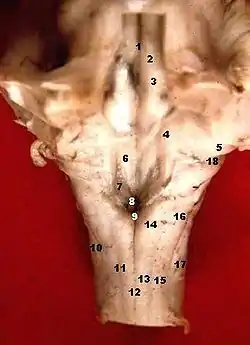

Human caudal brainstem posterior view description

Human caudal brainstem posterior view description